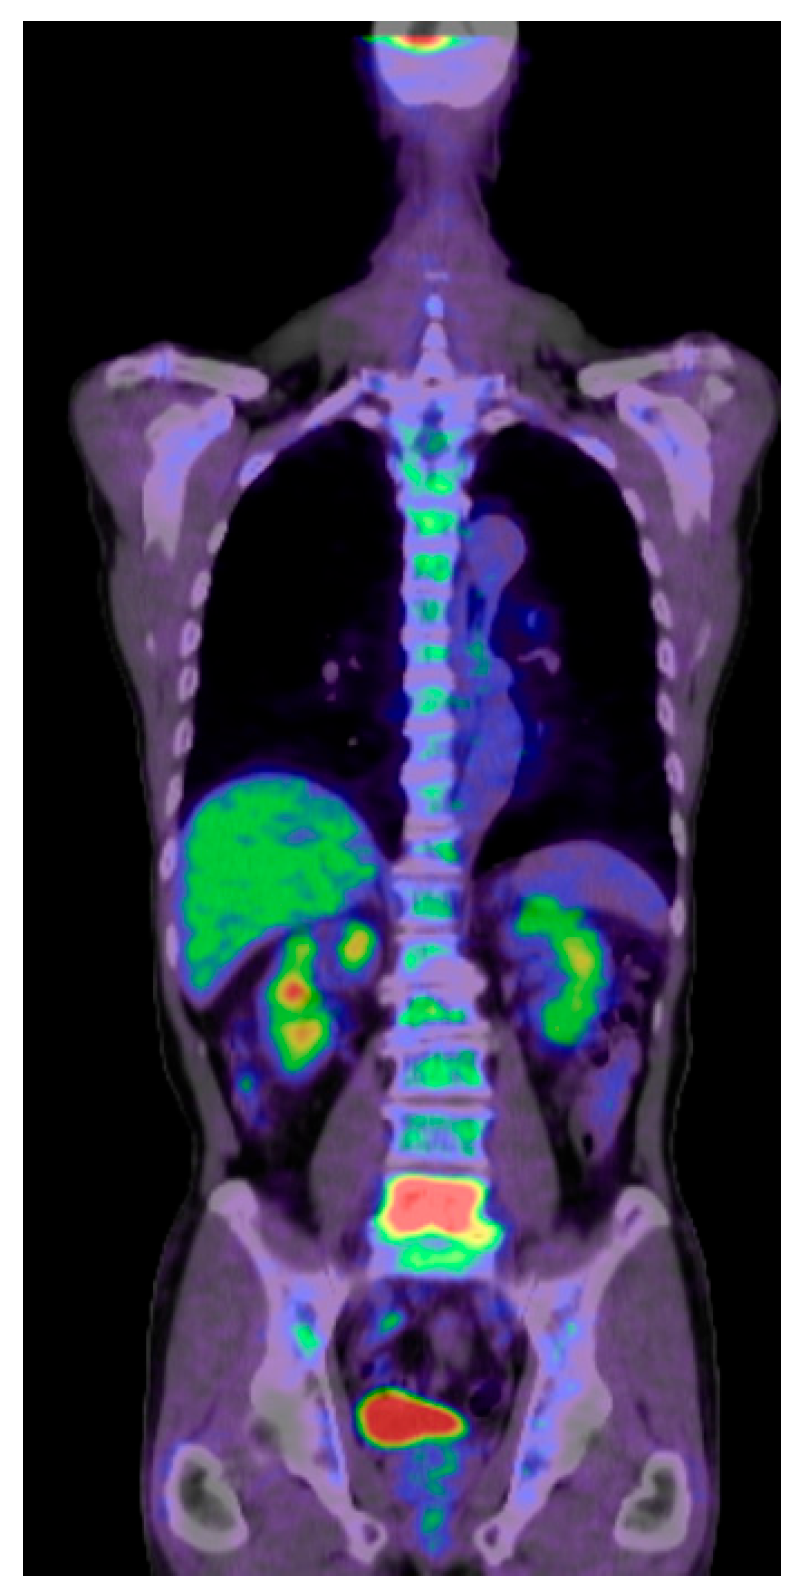

3.2. Positron Emission Tomography (PET)

Positron Emission Tomography (PET) provides insights into metabolic processes by detecting the uptake of radiolabeled tracers in the anatomical regions where there is high cellular activity [41]. This nuclear medicine technique utilizes the functional data of PET with CT data, in which inflammatory lesions, infections, and tumors can be detected and assessed [42,43,44] (Figure 4). 18F-fluorodeoxyglucose (FDG) is the most widely used tracer, an analog of glucose. Malignant processes have a high glycolytic rate. Therefore, it is typically detected by PET/CT as strong FDG uptake. The other tracers, such as 11C-methionine, 68Ga-DOTATATE, or 18F-fluoride, are also utilized for specific tumor types or bone metabolism studies. However, no consensus exists on their usage in spine pathology [45,46].

Tumor diagnosis and staging is one of the most commonly used areas of PET/CT. This technique provides superior data to detect occult changes that are not detectable with MRI or CT [47]. Moreover, this technique is also widely used in infectious or inflammatory processes of the spine, in which FDG uptake is high [48]. Dias et al. reported that out of 4463 lesions, diffusion-weighted (DW) MRI had a pooled sensitivity and specificity of 83% and 91%, respectively, compared with 78% and 81% for LPET/CT [49].

Figure 4. Seventy-two-year-old M, metastatic spinal tumor from maxilla cancer, PET CT, maxilla, and L5 are high uptake.